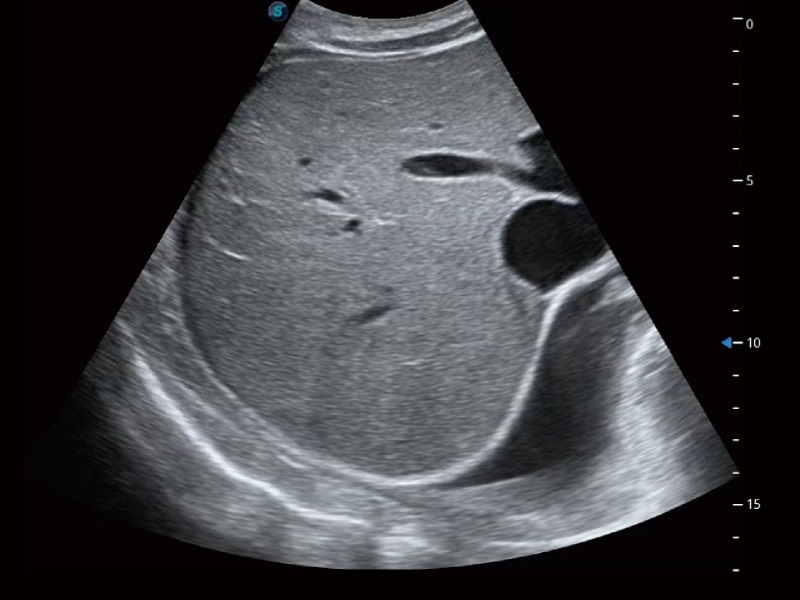

腹部应用

超声检查得益于实时性、经济性、便捷性,目前广泛的应用于临床工作中,超声检查设备已成为帮助临床医生轻松地完成诊断工作的好伙伴。P20 Plus集成了一整套包含了腹部、心血管、小器官、妇产科等全面临床应用功能,轻松应对各种临床问题。